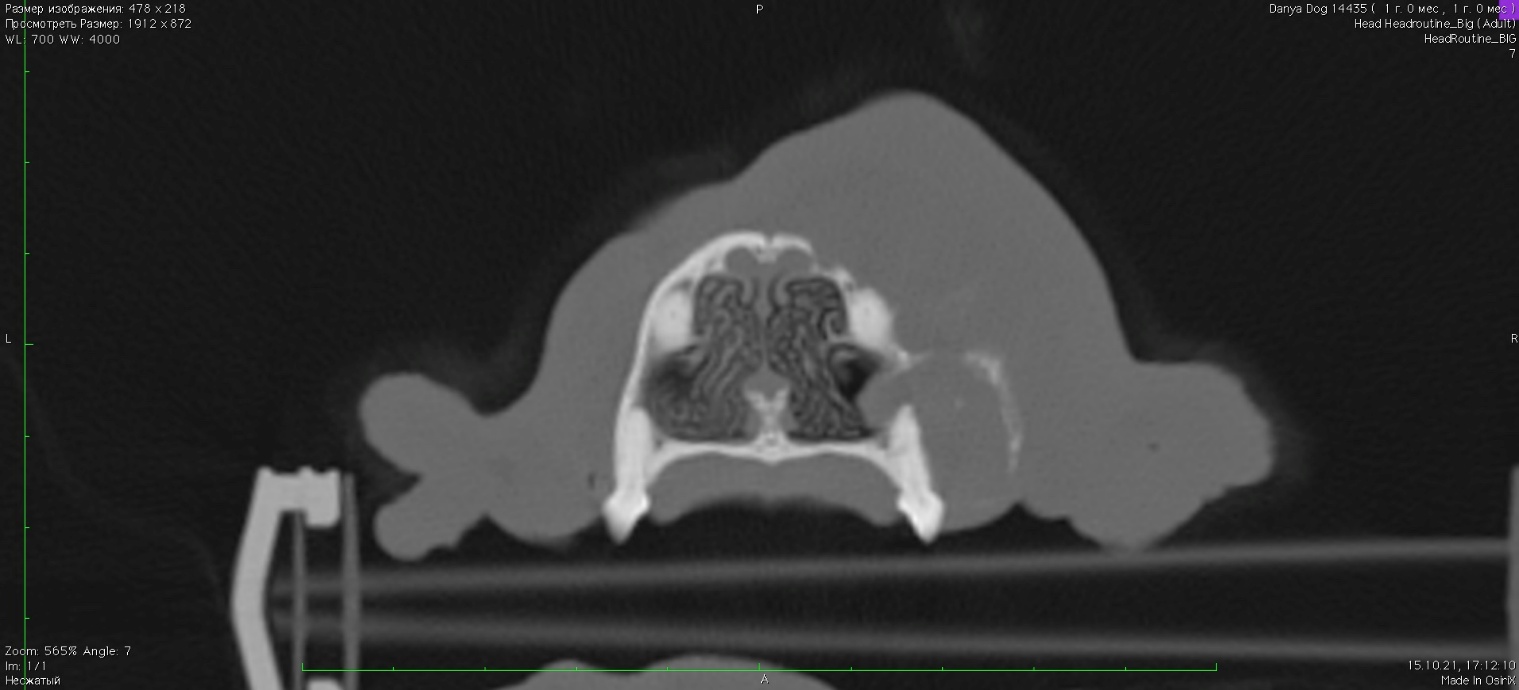

Отмечается частичный лизис кости верхней челюсти справа в зоне клыка и премоляров. В постконтрастную фазу отмечается очаговое образование с накоплением контраста в области верхней челюсти справа (зона клыка и премоляров) размером 17 х 25 х 17 мм. Отмечается незначительная инвазия опухоли в правый носовой ход (изоб.2).